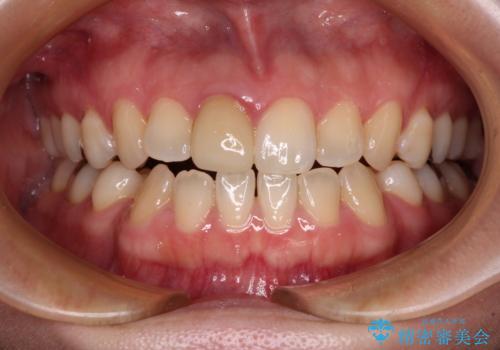

ワイヤー矯正後の後戻り 出っ歯を治したい マウスピース矯正

インビザライン・モデレートを用いて気になる後戻りを矯正治療